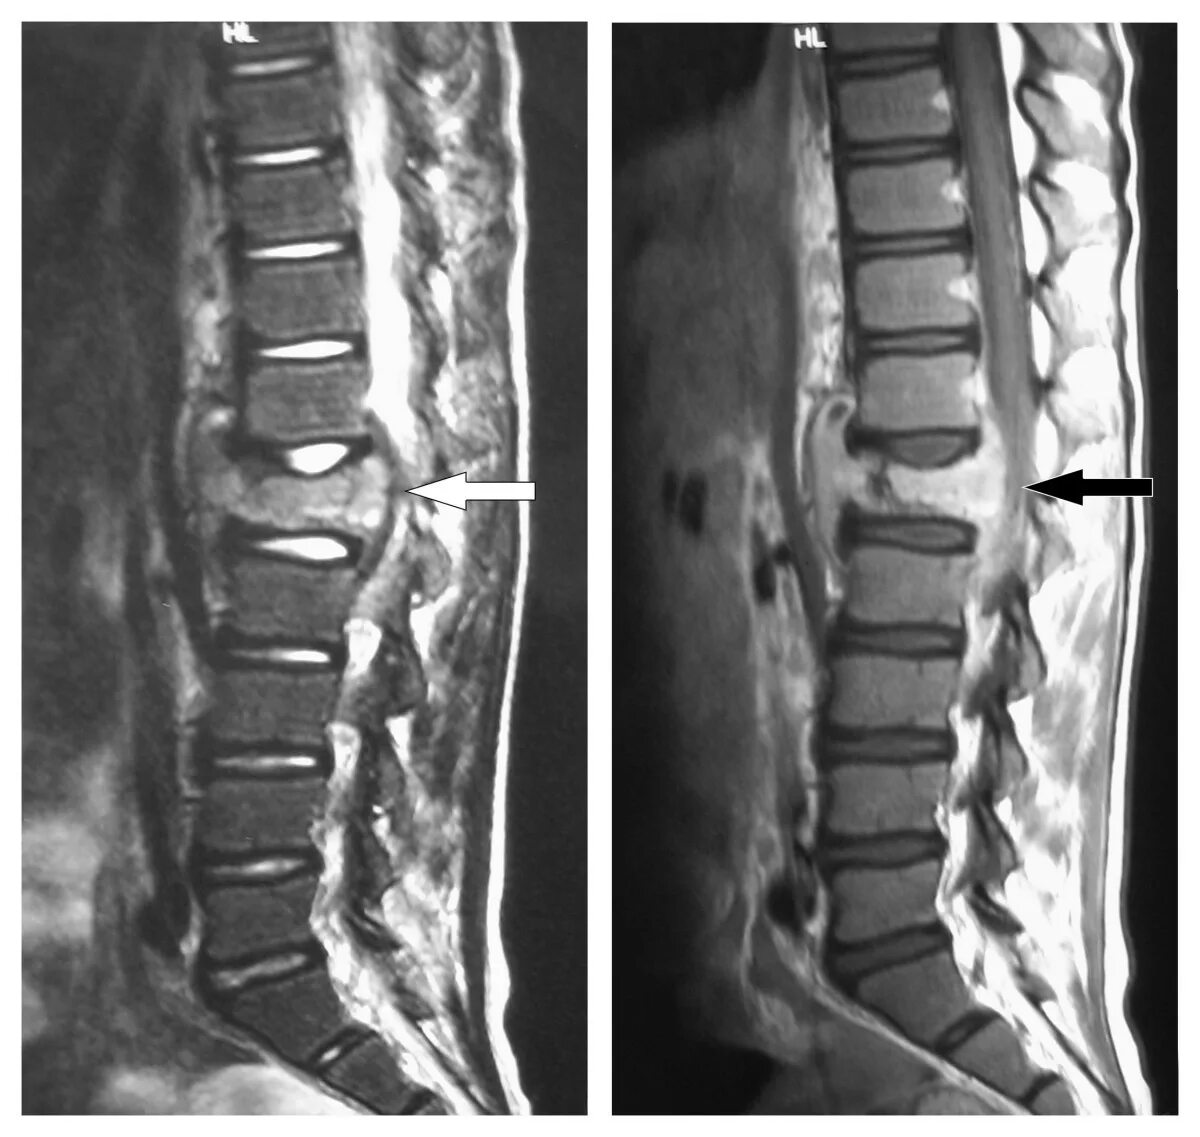

Мрт поясничного отдела подготовка к процедуре